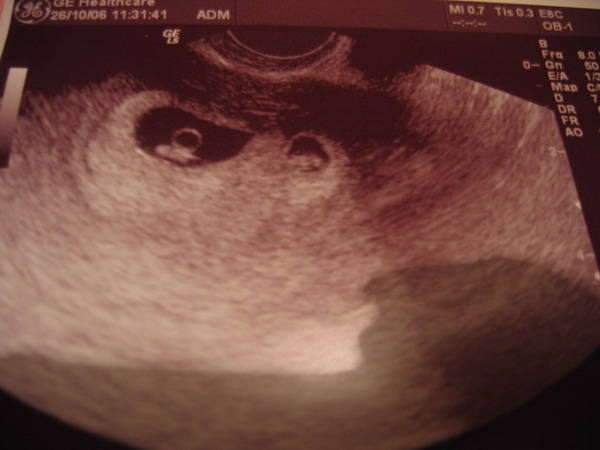

Ma voltam UH-on.

Egy picurkánk van, ennek megfelel?en csináltam vonalzót.

13 mm-es a petezsák. Következő UH november 7.